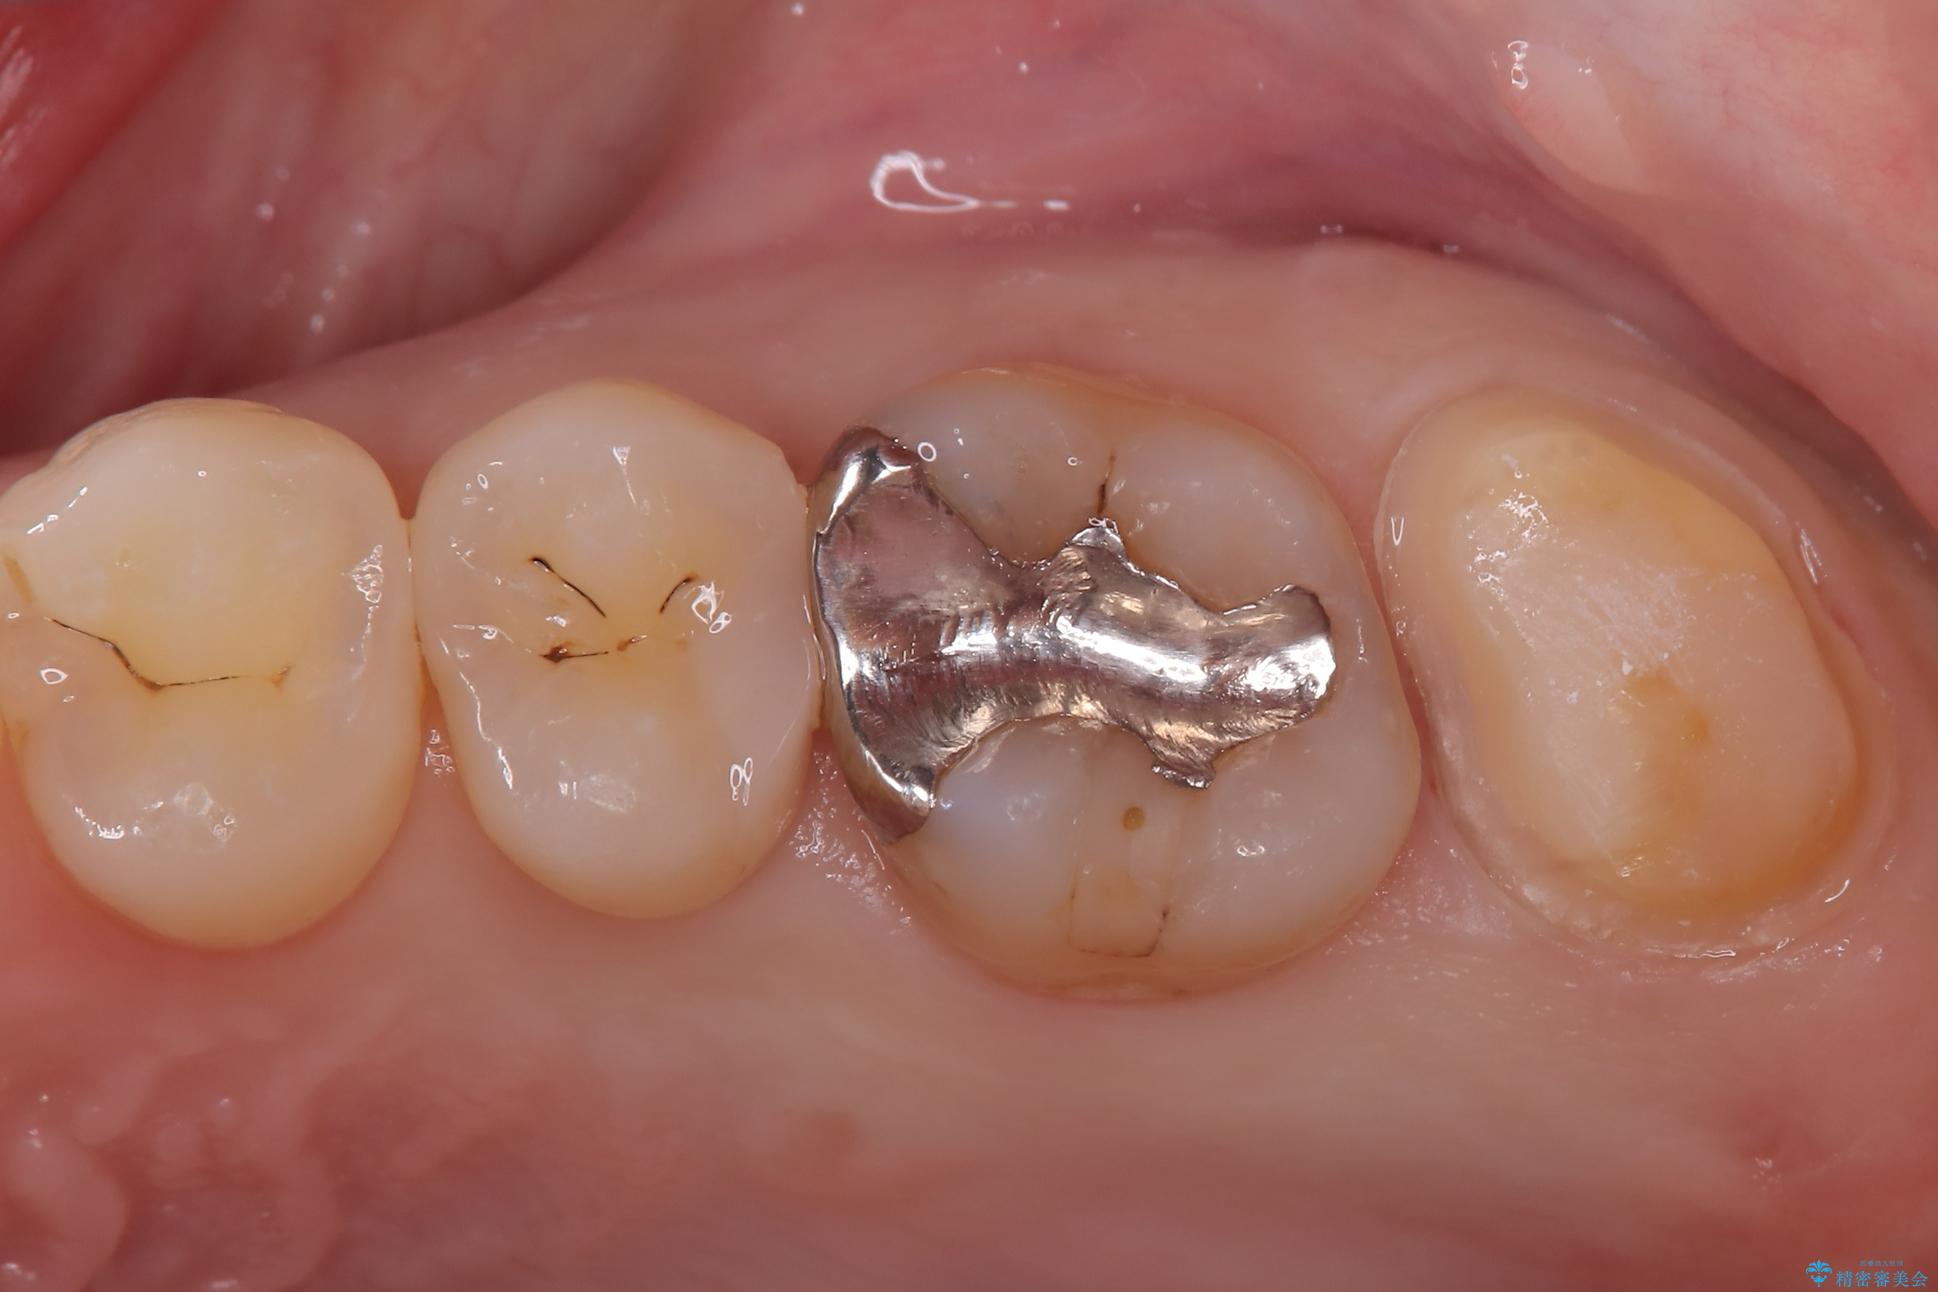

- 「冷たいものが強くしみる」という主訴でご来院されました。精密な診査の結果、虫歯が非常に深く、通常であれば神経を全て抜く「抜髄(ばつずい)」が必要な状態でした。しかし、神経を抜くと歯の寿命が縮まってしまうため、今回は神経の一部を温存する**「部分的断髄法(VPT)」**を提案しました。高い殺菌性と封鎖性、そして組織の再生を促す効果を持つMTAセメントを使用して神経を保護し、最終的には強度と審美性に優れたセラミックで修復する計画を立案しました。

部分的断髄法(MTAの使用): ラバーダム防湿を行い、無菌的な環境下で虫歯を慎重に除去。神経の露出を確認した後、炎症を起こしている一部の神経のみを除去し、残りの健全な神経を保護するためにMTAセメントを充填しました。これにより、神経の機能を維持し、歯を内部から守ることが可能となりました。